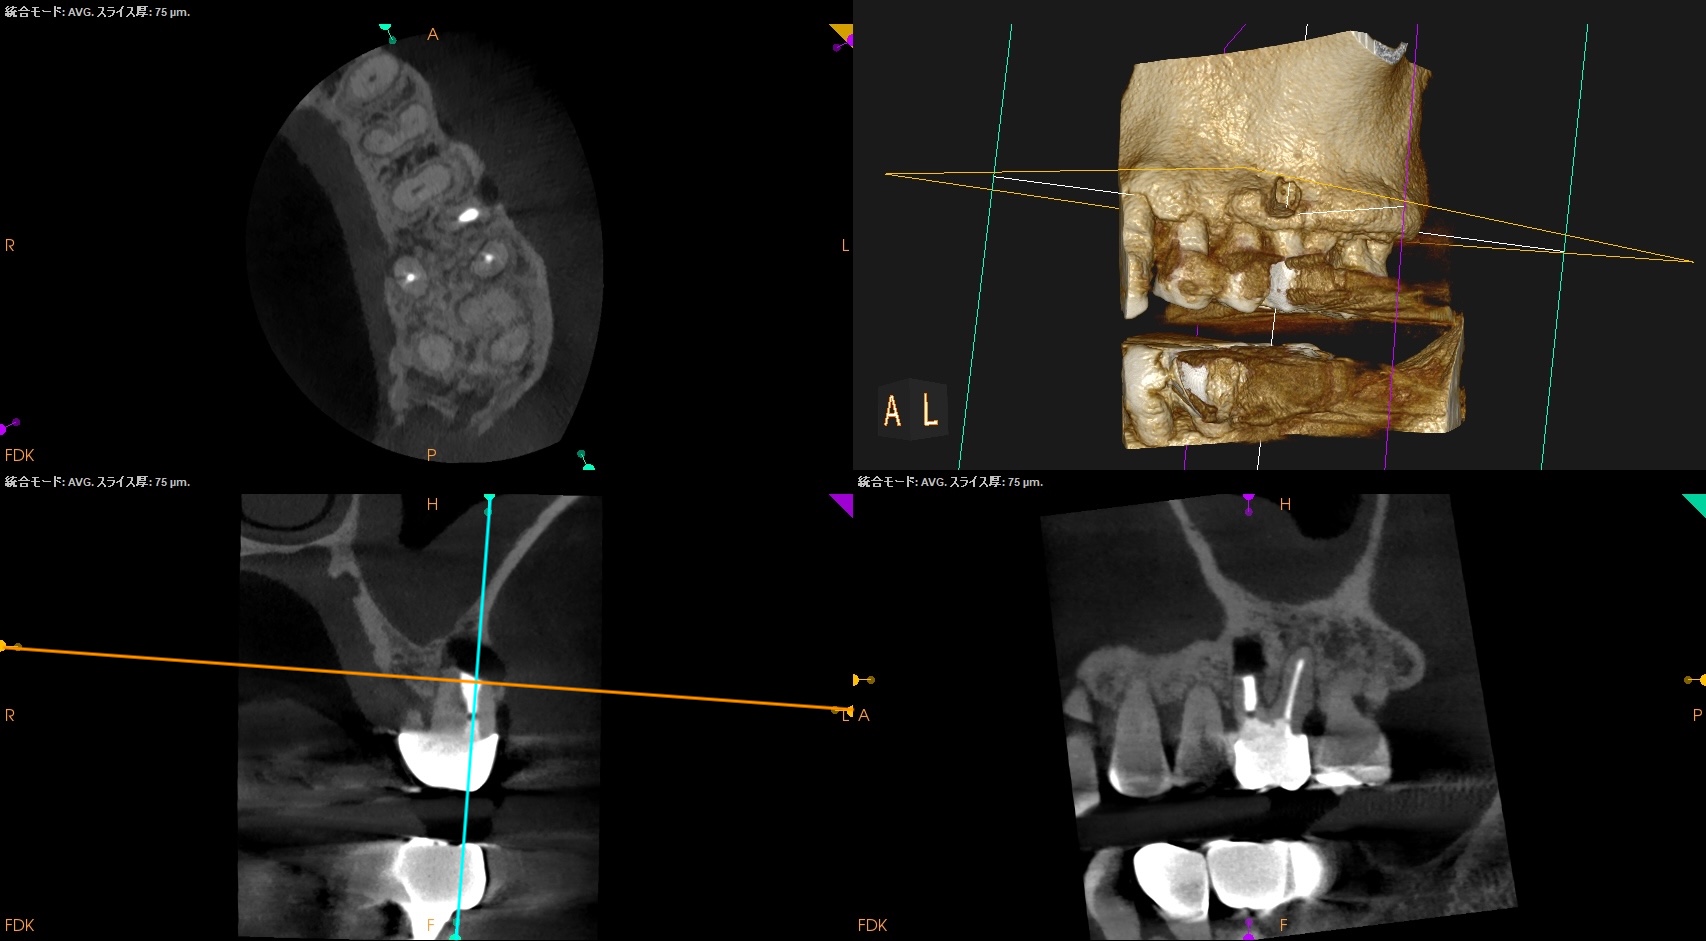

PA, CBCTを撮影した。

逆根管充填材が頬側に寄っているような絵である。

が、だ。

これはこのような切断部位で観察していることになる。

いわゆる、

歯軸と並行でないのである。